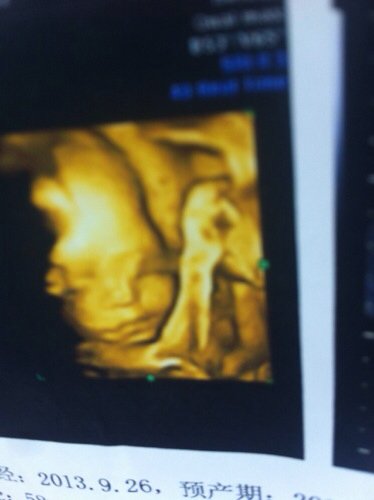

宝宝四维照片好奇怪,怎么感觉鼻子缺一块的,两只眼睛也不对称,急死了,帮忙看看 点击展开 匿名用户 2014-04-22 18:00 为您推荐: 其他回答 小宝宝嘛,身体各部分还没发育完全,而且现在的医疗设备也只能探测到大概一部分.我觉得您的宝宝在同类中已经算眉清目秀了.你的宝宝很健康,不用担心 绳梦菡_iOsP 2014-04-22 18:17 见鬼了,不过可能是还没发育好 匿名用户 2014-04-22 18:12 哪有宝宝,是那么清楚的,别担心。 匿名用户 2014-04-22 18:05 相关问题 这张四维彩超图有问题吗?感觉鼻骨歪的还有眼睛不对称,帮忙看下、谢谢了 怀孕七个半月,不小心把修鞋的胶水弄到手上,刺激到鼻子和眼睛,眼睛但是还疼了一小会,请问这样对宝宝有 今天去拍了四维,宝宝太像我了鼻子嘴巴像完,而且是千金哦